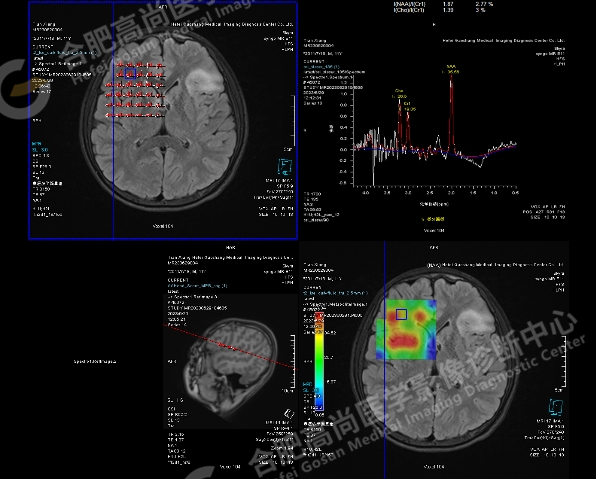

MRS 示:左侧病灶感兴趣区 NAA 24.83,Cho 26.46,Cr 14.43,NAA/Cr1 1.72,Cho/Cr1 1.83;右侧对照区 NAA 35.56,Cho 26.50,Cr 19.05,NAA/Cr1 1.87,Cho/Cr1 1.39。病灶提示神经元轻度减少。

加做 ASL 血流灌注显示左额叶病灶区局部灌注异常,呈稍高信号。

头颅 MRI 高分辨及功能成像:可用于进一步观察细微结构,也可利用功能成像,如,ASL 观察组织血流灌注情况,且无需静脉注射造影剂;MRS 可以敏感地测定局部脑区重要的代谢物浓度,从而反映病灶的病理改变,如 NAA 峰值降低提示神经元数目减少,Cr 和 Cho 峰值升高提示胶质增生。